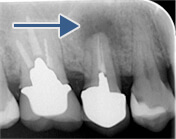

レントゲン写真により経過を確認します

黒い影は骨が溶け膿を持っている

黒い影が無くなり骨の再生が認められ経過は良好です